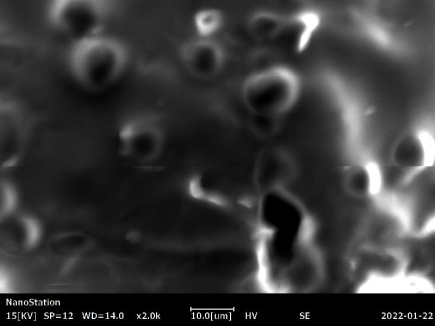

SEM (Hitachi S3400, Tokyo, Japan) was used to analyze the surface morphology of nanoparticles. This is performed to describe how dilution affects the nanoparticles' surface morphology. An aluminum stabu (plate) was used to collect the nanoparticles sample. The instrument's stabu was inserted after being wrapped in carbon tape for insulation. SEM images were acquired after a vacuum was applied [18].

Scanning electron microscopy (SEM)

More information regarding particle size and shape of F2-SLNs dispersion was obtained using scanning electron microscopy. Nanoparticles photographed for SEM is shown in fig. 4. The nanoparticles were uneven in shape, as evidenced by SEM images. Drug loading and release behavior of nanoparticles might be affected by particle shape. SEM image describes that the particles have uniform loose aggregates, spherical in shape with a smooth surface and they are uniformly distributed. Solid lipid nanoparticles of rivastigmine tartrate were found to be spherical and irregular and their surface was smooth and devoid of cracks giving them good appearance. These results were similar to research supported by Kulkarni et. al, 2018 [23].

Fig. 4: Scanning electron microscopy of F-2 solid lipid nanoparticles